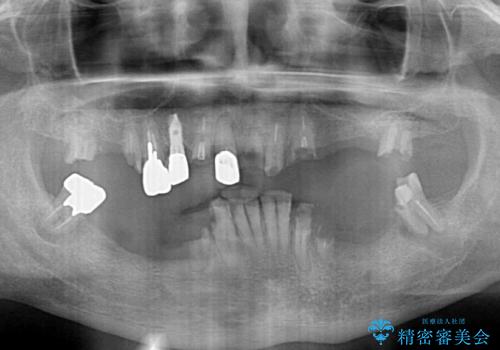

- どこで咬んでよいのか分からないとのことで来院された患者様です。

歯冠の崩壊した奥歯と、前歯の一部でした咬み合うことができず、入れ歯も試したものの、装着することができなかったようです。

全顎的にインプラント補綴を行うことも検討しましたが、費用面から、インプラントを土台とした入れ歯(インプラント・オーバーデンチャー)による補綴治療を行うこととしました。